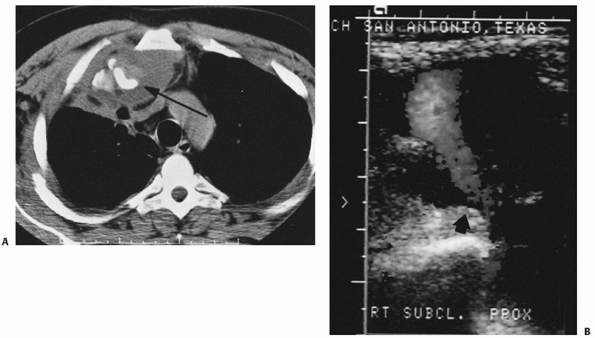

FIGURE 40-12 A. Routine anteroposterior radiograph of posteriorly dislocated right SC joint. B.

The anteroposterior view is suggestive of a posterior dislocation. However, the CT scan clearly demonstrates the posteriorly displaced right medial clavicle. Note the displacement of the trachea. |